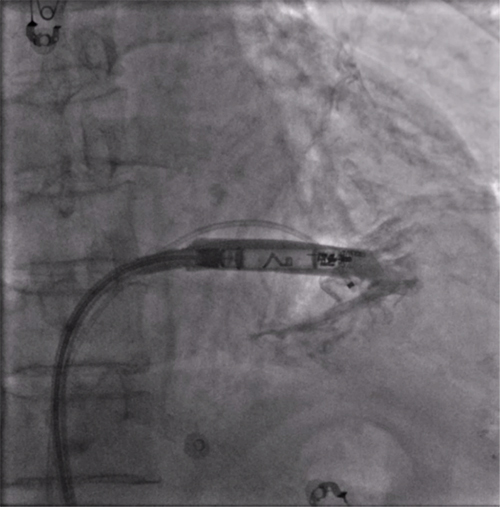

经过周密的术前准备,彭晖、孙志军两位主任带领邸北冰主治医师、柳晓娜主治医师和梁立丰医师在内的起搏电生理团队,于心脏介入手术室为患者实施手术。手术团队股静脉穿刺成功后,首先对下腔静脉进行造影并将外鞘放置送入下腔静脉,随后将新型主动固定螺旋无导线起搏器顺利跨瓣送入右心室目标位置,旋入前测试无导线起搏器各项电学参数良好,确认位置合适后旋入固定起搏器,在植入过程中动态测试起搏器各项参数以辅助判断固定程度,达到标准后进入对接栓模式,再次测试起搏器固定位置稳定、各项参数良好后释放起搏器,最后撤出鞘管,顺利完成手术。整个手术流程高效有序,医疗团队成员紧密配合,默契无间,仅耗时40分钟共同完成了这一具有挑战性的任务。

RAO造影确认位置安全

电学标测参数良好,在此旋入1.5圈后进入对接栓模式,

摇摆与电学参数测试后释放起搏器